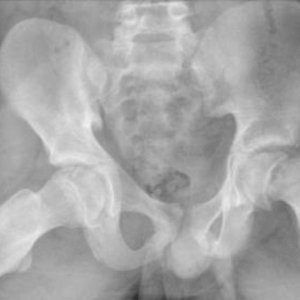

Developmental Dysplasia of the Hip (DDH)

Slipped Capital Femoral Epiphysis (SCFE)